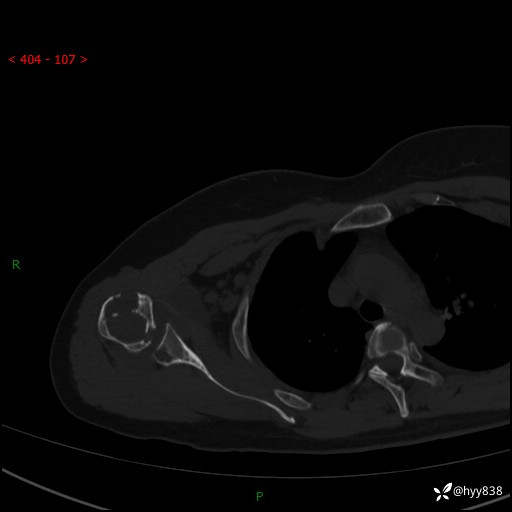

右肩关节CT平扫